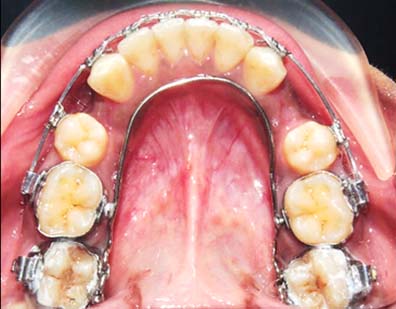

One month later uprighting of the ligually tipped mandibular second molars was noticed [Table/Fig-13].

Uprighting of the lingually tipped mandibular molars noticed after a month.